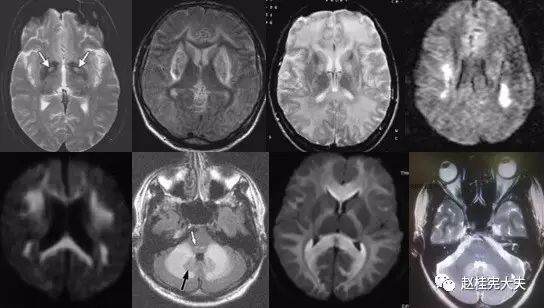

重要申明:以下每个部分会配磁共振图片,因疾病和影像之间存在同病异象、同像异病,为避免误导,图片不标注疾病,请各自鉴赏,另其中有部分图片来源于网络,有疑问可与本人联系。

一、M—metabolism 代谢性

代谢性脑病的原因很多,包括氨基酸、有机酸、脂肪酸、糖等代谢异常,以及线粒体功能障碍等,导致高氨血症、低血糖、酸中毒和能量缺乏,引起脑功能障碍。我们在临床上看到的有缺血缺氧性脑病、低血糖致白质脑病、肝性脑病、肾性脑病、Wernicke脑病、线粒体脑病等。中枢神经系统受累的病灶在磁共振上可出现各种表现。

T--toxication,中毒/trauma,外伤。

个人认为这里的中毒理解为毒物相关的病变更合理一些。

如酒精中毒相关的,如MBD。

各种中毒,有机溶剂,如苯、甲醇、一氧化碳中毒、氨己烯酸中毒等。

毒品如海洛因、可卡因等。

抗肿瘤或免疫抑制剂如甲硝唑、5-FU(5-氟尿嘧啶)及其前体药物卡培他滨、他克莫司、甲氨蝶呤、贝伐单抗等相关性脑病。